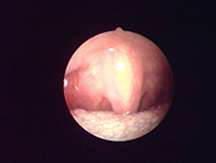

經典案例